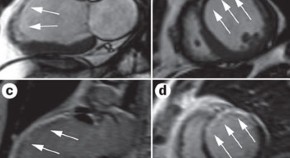

• Areas of thinned myocardium (≤5.5 mm) were previously thought to be regions of transmural infarction, without remaining viable tissue. However, new data using late-enhancement cardiovascular magnetic resonance imaging now show that, in 18% of patients with ventricular wall thinning, substantial viable myocardium remains, which can improve in function after revascularization.

• Jeroen J. Bax